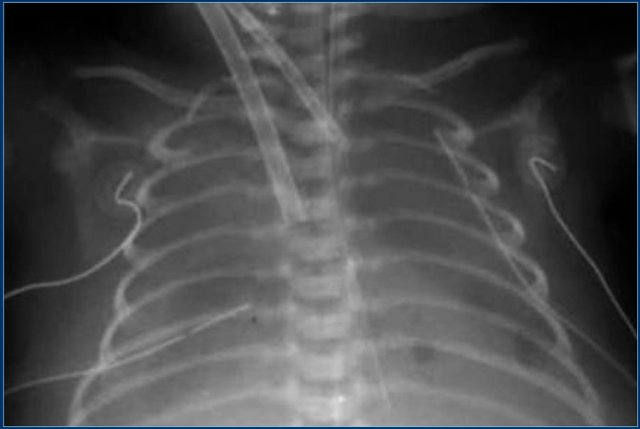

Umbilical venous line (8 )

Study the images.

Then continue reading.

The findings are:

• The umbilical venous line is too deep

• After repositioning the tip is in a good position.

Notice that the endotracheal tube is too deep.